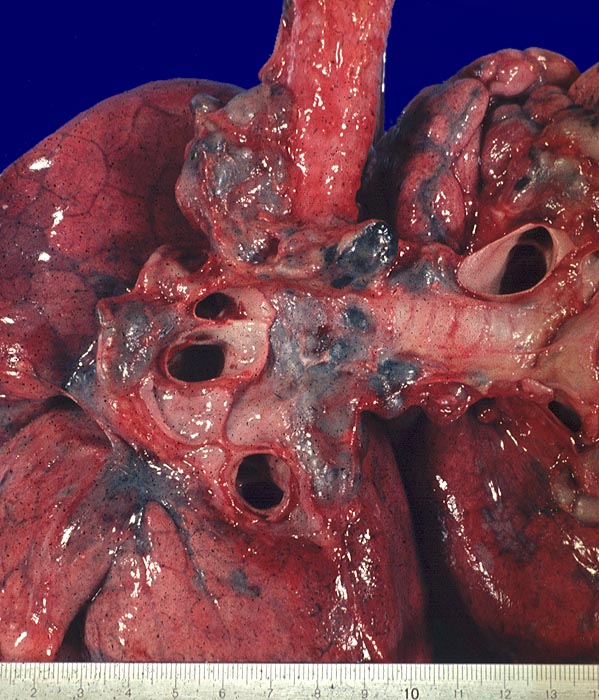

Jedes Organ kann befallen werden. Besonders häufig erkranken: Lunge (95%) und mediastinale Lymphknoten (ca. 75–100%), Auge, Milz, Leber, Bronchialschleimhaut (ca. 25–50%), Haut und periphere Lymphknoten (ca. 33%), Knochen, Herz, Niere, Nervensystem und Muskulatur. Die nicht-nekrotisierenden Granulome sind oft in der Submukosa der Bronchialschleimhaut lokalisiert und können in bronchoskopisch entnommenen Biopsien nachgewiesen werden.

Die Morphologie der Erkrankung ist stadienabhängig. Initial findet sich eine lymphozytenreiche Alveolitis mit wenigen kleinen Granulomen. Die Granulome bestehen aus Aggregaten epitheloider Histiozyten teilweise mit Beteiligung von mehrkernigen Riesenzellen. Im Verlauf entwickeln sich zellreiche Granulome entlang der bronchovaskulären Bündel und der Interalveolarsepten, welche später konfluieren und vernarben. Die Riesenzellen können Asteroidkörperchen (sternförmige Kristalle) oder Schaumannkörperchen (lamelläre Verkalkungen) enthalten. Ein Teil der Patienten entwickelt eine irreversible Lungenfibrose.

Die Krankheitsaktivität wird anhand der Klinik, des Röntgenbefundes und der Lungenfunktion bestimmt, seltener durch Bronchoalveoläre Lavage (CD4/CD8-Zellquotienten) oder Serum-ACE Wert (Angiotensin converting enzyme). Die häufigste Veränderung im Thoraxröntgenbild stellt die bihiläre und mediastinale Lymphknotenvergrösserung dar. Verschiedene Formen von Lungeninfiltraten, Fibrose und Narbenbildungen können hinzukommen. Zur Bestätigung der Diagnose ist in den meisten Fällen eine Biopsie erforderlich. Meist wird eine Bronchusbiopsie durchgeführt (in 70-80% positiv). Hiläre Lymphknoten, Haut, Konjunktiva oder Lippe können ebenfalls biopsiert werden. Biopsien aus der Leber oder Scalenuslymphknoten sind ungeeignet, da Granulome in diesen Lokalisationen sehr unspezifisch sind. Die Sarkoidose lässt sich beweisen mit einer Broncho-Alveolären Lavage (BAL) mit einer Sensitivität von >90% wenn: Lymphozytenzahl 40–60%, > 90% T-Zellen und T4/T8-Quotient > 2 (normal: 1,6).

Makroskopie